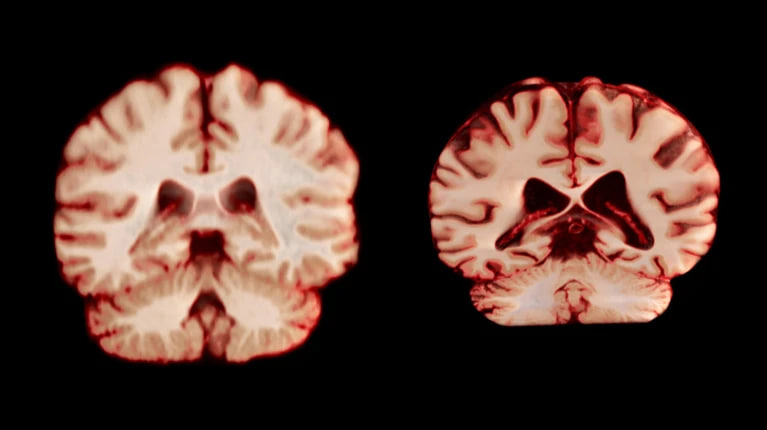

Erkaklar ayollarga nisbatan tezroq qarishi ilmiy jihatdan isbotlandi

Bu miya hajmining kamayishi bilan izohlanmoqda.

Yosh o‘tishi bilan erkaklarda miya hajmi ayollarga qaraganda kuchliroq va ko‘proq sohalarda kamayadi. Proceedings of the National Academy of Sciences jurnalida chop etilgan va yaqinda o‘tkazilgan tadqiqot natijalari shuni ko‘rsatdi.

Bu esa erkaklar ayollarga qaraganda tezroq qarishini, umr ko‘rish davomiyligi ham qisqaroq bo‘lishini anglatadi.

Umuman olganda, erkaklarda ayollarga qaraganda miyaning ko‘proq sohalarida hajmning sezilarli darajada kamayishi kuzatildi. Masalan, taktil, og‘riq va harorat sezgilarini qayta ishlash, shuningdek, tananing o‘z holati va harakatlari uchun mas’ul bo‘lgan postmarkaziy po‘stloq ularda yiliga 2,0 foizga, ayollarda esa 1,2 foizga qisqargan.